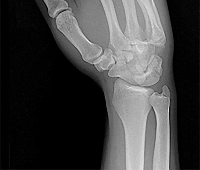

Question 7:

A 40-year-old weekend warrior sustains an acute Achilles tendon rupture. Nonoperative management is chosen. Which of the following protocols has been shown to result in outcomes similar to surgical repair regarding re-rupture rates?